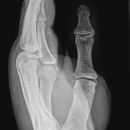

Hand streng seitlich: radio-ulnar

Dient zur Bestimmung der Luxationsrichtung bei Carpometacarpalen oder Metacarpophalangealen Luxationen (meist dorsal) oder zur Bestimmung des Dislokationsausmaßes metacarpaler oder phalangealer Frakturen.

Cave: Metacarpale und phalangeale Rotationsfehlstellungen sind konventionell röntgenologisch schwer zu diagnostizieren und zu quantifizieren -> klinischer Befund führend (Fingerstrahl kreuzt bei Beugung im Grundgelenk den benachbarten Strahl), evtl. CT hilfreich.